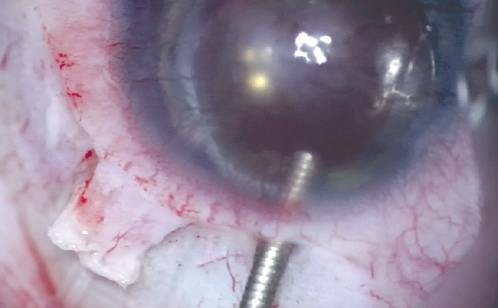

- Retraction of the tube in one eye (1.5%), namely, displacement of the tube end to the limbus zone due to eyeball stretching. The valve platform was displaced anteriorly (Fig. 7).

Fig. 7. Tube retraction / Рис. 7. Ретракция трубки